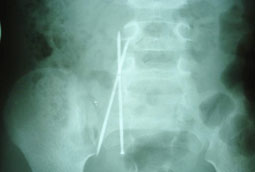

استخراج إبرتين من بطن طفلة بالمنظار الجراحي

تمكَّن الفريق الطبي بمستشفى الولادة والأطفال ببريدة بنجاح تام من وضع حد لمعاناة فتاة صغيرة (ست سنوات) كانت تعاني من آلام مبرحة وحادة في بطنها مما أعيى والديها في مراجعة عدد من المشافي بالمنطقة، حتى اكتشف استشاريي الجراحة بالمستشفى وجود إبرتين طويلتين داخل التجويف البطني للصغيرة.

وعلى الرغم من الحيرة التي انتابت الوالدين والأطباء في كيفية حدوث ذلك، إلا أن الأطباء باشروا على الفور معالجة الحالة، وتم إعادة التصوير الإشعاعي من عدة جوانب، ومن خلال التدخل الجراحي بالمنظار تم استخراج إبرة واحدة فقط في حين تعذّر استخراج الأخرى إلا بعد عملية الفتح الجراحي، وذلك لما ينطوي عليه موقع الإبرة من تعقيدات، إذ إنها كانت تقبع بين الأوعية الدموية.